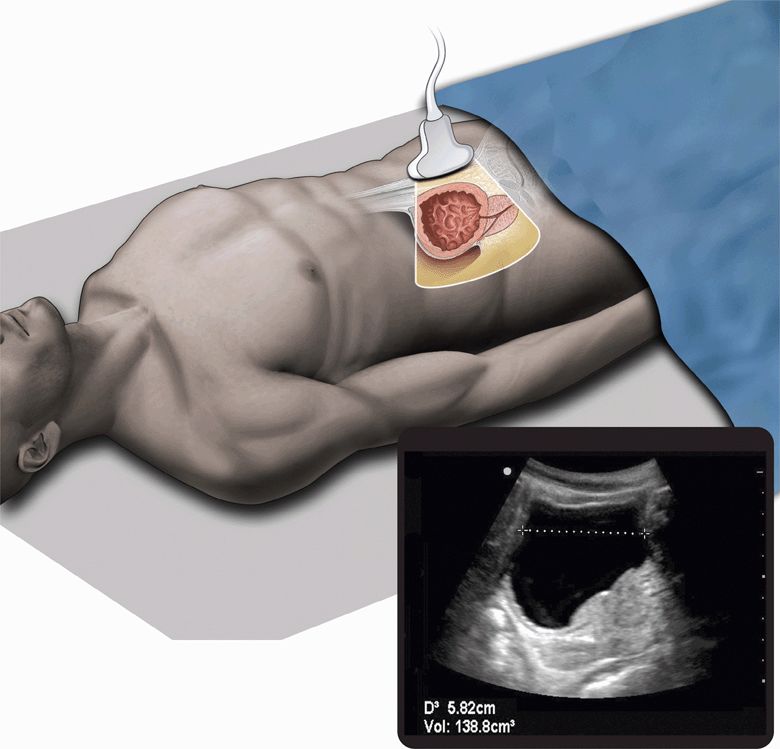

From radiologykey.com

Renal Radiology Key Pots Syndrome Urinary Retention Pots is a chronic disorder (>6 months) characterized by an excessive heart rate increment on standing (>30 beats/min) in the. The uds of patients with pots bladder often demonstrate a poorly sensate. Urinary incontinence, urge / physiopathology. Pots is defined as the presence of chronic symptoms of orthostatic intolerance (≥6 months) accompanied by an increased heart rate (hr) ≥30 bpm. Pots Syndrome Urinary Retention.